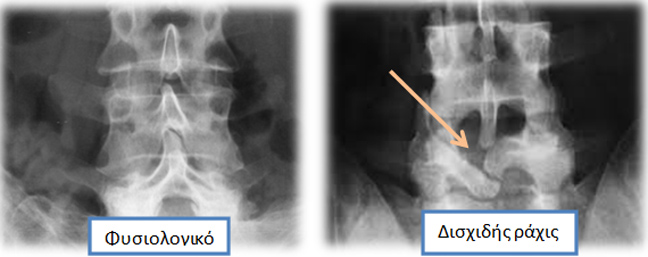

Η δισχιδής ράχις (Spina Bifida) δεν είναι πάθηση. Είναι ανατομική κατάσταση που ανακαλύπτεται τυχαία σε άτομα με οσφυαλγία που υποβάλλονται σε ακτινολογικό έλεγχο.

Η δισχιδής ράχις οφείλεται σε ατελή σύγκλειση του τόξου που περιβάλλει τον νωτιαίο σάκκο και κλείνοντας δημιουργεί την ακανθώδη απόφυση

Η δισχιδής ράχις είναι τυχαίο ακτινολογικό εύρημα και δεν δίνει κλινικά σημεία στην εξέταση.